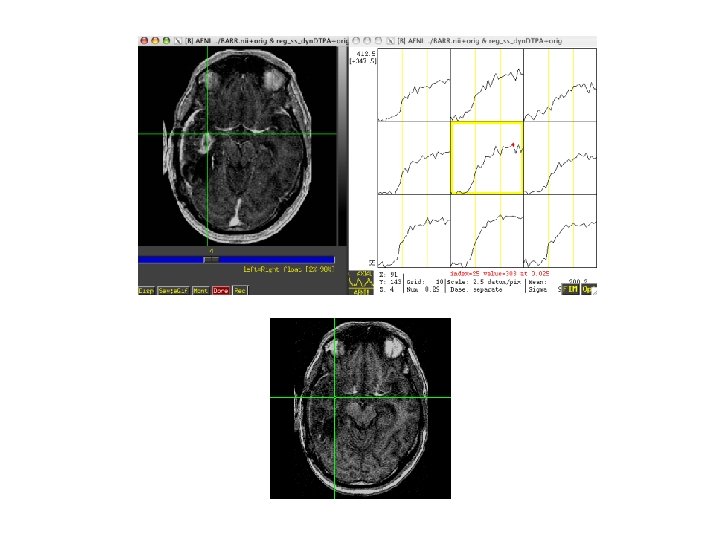

Rat brain

Steps • Volume register • Identify sagittal sinus ROI can calculate Mp(0) for first

Steps • Volume register • Identify sagittal sinus ROI can calculate Mp(0) for first few TRs, Mp(t) • Calculate Cp(t), Gd concentration in plasma, with nonnegative constraint • 3 d. Automask to limit voxels to brain or specify ROI • Also normalize to ratio of first few TRs and limit voxels of interest to those that change by at least 10% over the average of last five time points • May want to separate blood and tissue with two ROIs to use a single intrinsic relaxivity at a time (Gyrus Finder Plug-in? ) • 3 d. NLfim - calculate fit of Ktrans, kep, fpv given Cp(t), R 1, I, TR to the normalized m(C, T) • m = f(C, R 1, I), C=f(Ct, fpv, Cp(t)), Ct=f(Cp(t), ktrans, kep or Ve) • final fit parameters = Ktrans, kep, fpv for each voxel